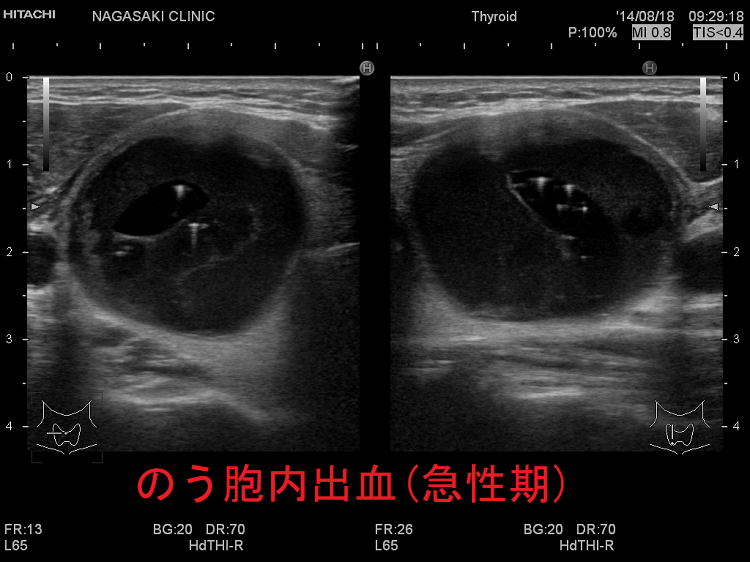

- のう胞内出血(嚢胞内出血);甲状腺エコーで一目瞭然